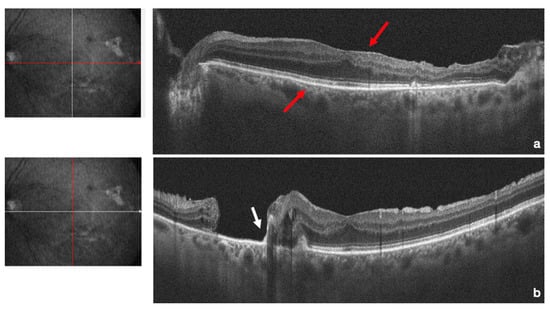

2. Case Report